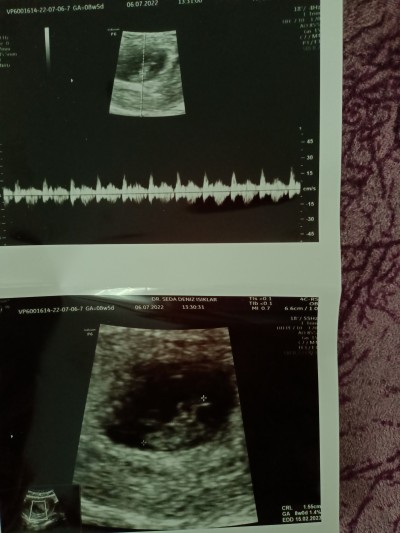

Arkadaşlar merhaba 8 haftalık gebeyim.Dun doktor herhangi bir sıkıntı olmadığını söyledi kalp atışları da normal ama ultrason fotoğrafında bebek neden net değil ya da bana mı değişik geliyor ?

Gebelik haftası 8

Bu haftalarda böyle oluyor 12 13 haftalık olunca net oluyo başı gövdesi falan bnde 9 haftalığım böyle ultrason resmi

Eğer alttan ultrason ile çekilirse daha net çıkar benm ilk gebelikte alttan 7 haftalık ultrasonda dha netti mesela bu defa 9 haftalık karnımdan hiç bişey belli değil

Şuan muhtemelen uzaylı gibi bişey yani kuyruğu falan var. 10. Haftadan sonra insana benzemeye başlar.

Zaten o hafta kiraz büyüklüğünde oluyor nasıl seçilecek Allah aşkına :))

Şuan bebek diye gördüğünüz yolk kesesi. Bebeğin beslendiği yer. Bebeği şuan göremezsiniz ve vucudu şekilsizdir. 12. Haftadan sonra vucut şekline bakabilirsiniz şuan başını VS doktor bile büyük ihtimalle göremez